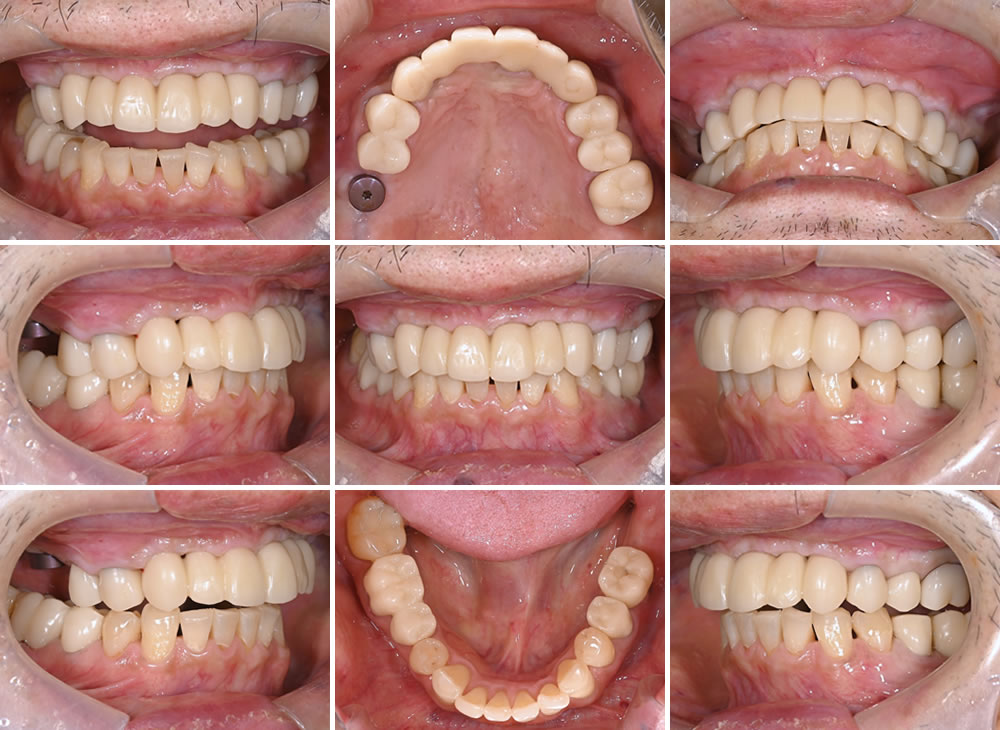

約3ヵ月後、型取りを行うための前処置を行いました。

型取り~仮歯の装着

型取りを行って仮歯を制作した後、前歯部分と奥歯に仮歯を装着しました。

最終的な上部構造(人工歯)の型取り

仮歯を約1ヵ月間使用していただいた後、機能的に問題がないことを確認しました。歯肉の状態も良好であったため、最終的な上部構造(人工歯)の型取りを行いました。